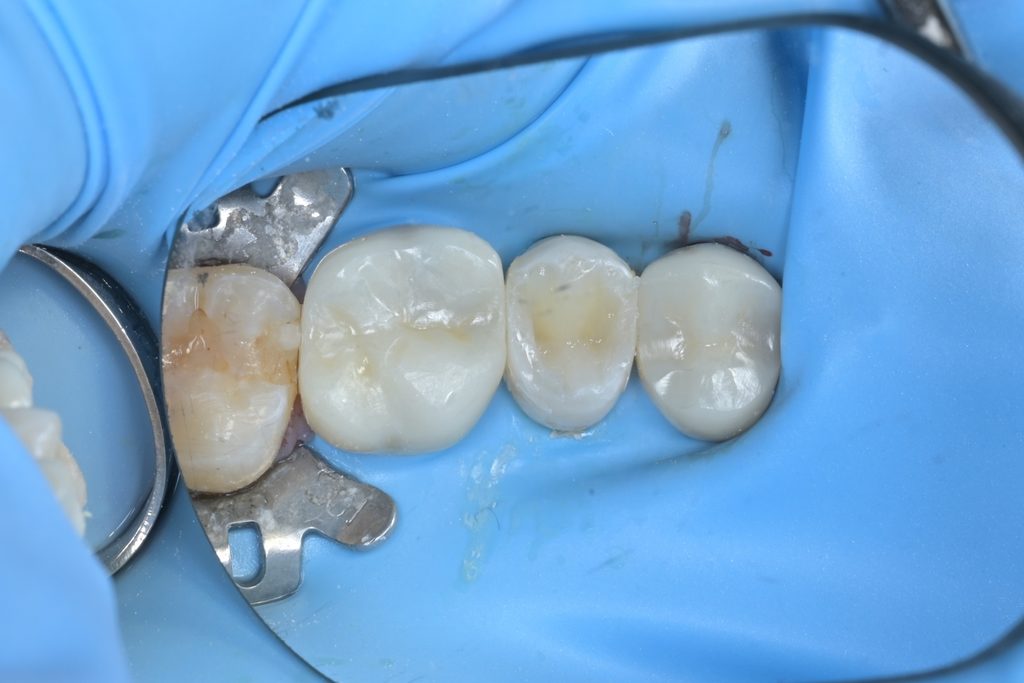

Step 1: 러버댐 격리

성공적인 치수 치료의 첫 단계는 완벽한 방습입니다. 치수가 침, 혈액, 세균에 오염되면 치료 성공률이 급격히 떨어지기 때문입니다.

Step 2: 우식 제거

미세현미경을 사용하여 기존 수복물과 우식 조직을 세밀하게 제거합니다. 우식검사액(Sable Seek)을 사용하여 남아있는 우식 조직을 염색하고, 건강한 치질만 남을 때까지 정밀하게 제거합니다.